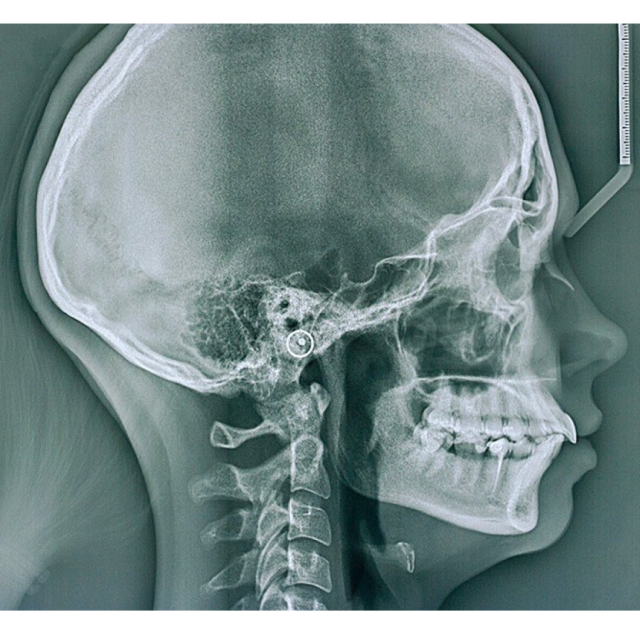

Radiographie de la tête d'un patient qui permet de dresser un bilan orthodontique

Le bilan orthodontique

Il s’agit du 2ème rendez-vous.

Avant ce RDV, plusieurs éléments seront nécessaire :

• Des photos du visage et de la dentition avant le début du traitement.

• Des empreintes numériques maxillaire et mandibulaire grâce à notre caméra intrabuccale 3 shape®

• Une radiographie panoramique

• Une téléradiographie sagittale et son analyse céphalométrique par des tracés permettant d’identifier la malocclusion et son origine.

Une fois ces éléments recueillis, le diagnostic final et le plan de traitement pourront être établis, et seront présentés au patient. Les modalités du traitement orthodontique seront exposées, tant en termes d’organisation des séances de soin et de durée de traitement, qu’en terme financier avec la réalisation d’un devis personnalisé en fonction du type d’appareil.